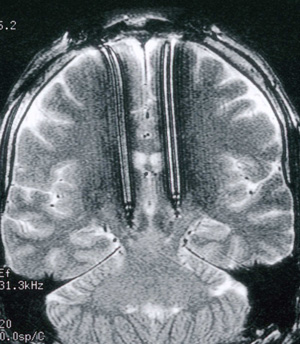

All surgical procedures were performed at The Royal Melbourne Hospital. Box 1 shows the positioning of the electrodes.

1: Position of stimulating electrodes

Electrodes inserted under local anaesthesia after physiological localisation of subthalamic nuclei and optimal motor response while patients were not taking medication. Pulse generators were subsequently implanted in chest wall and connected under general anaesthesia.8,9